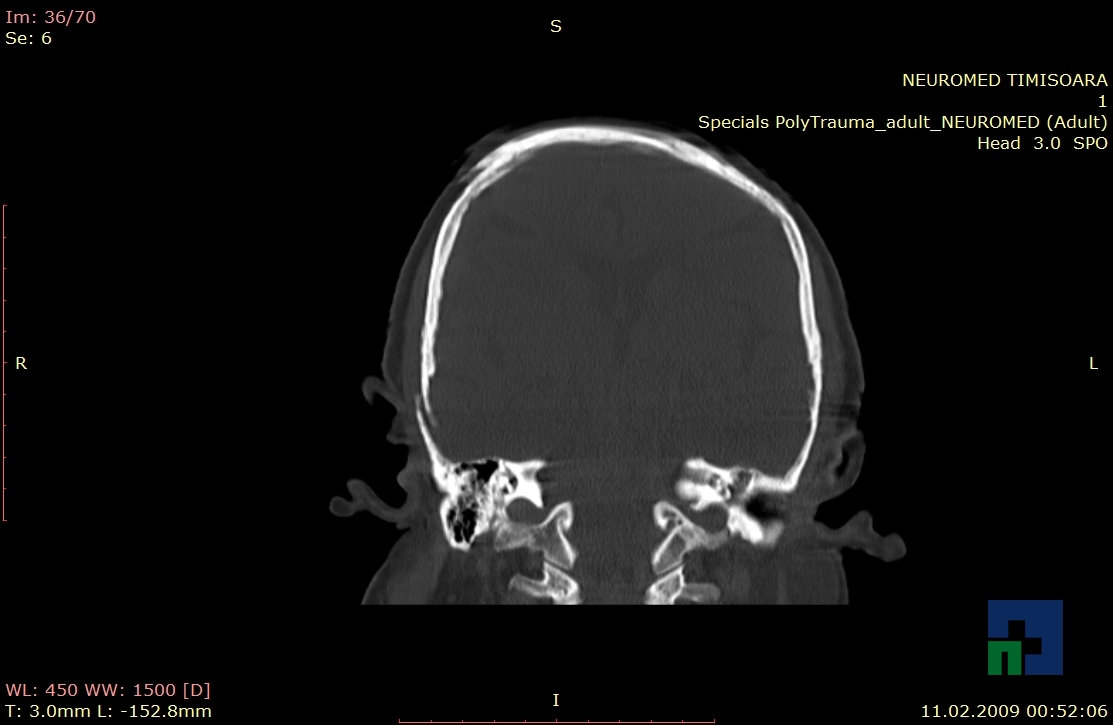

În cazul traumatismelor cranio-cerebrale:

- Evaluarea deplasării liniei mediane

- Evaluarea cisternelor perimezencefalice

- Diagnosticul edemului cerebral, a contuziei cerebrale, a leziunilor axonale difuze edematoase/hemoragice, a dilacerării cerebrale, a hematomului intraparenchimatos posttraumatic, a hematoamelor subdurale/extradurale (acute, subacute, cronice), a hemoragiei intraventriculare, a hemoragiei subarahnoidiene

- Diagnosticul traumatismelor de bază de craniu

- Diagnosticul herniilor cerebrale

- Diagnosticul fracturilor: